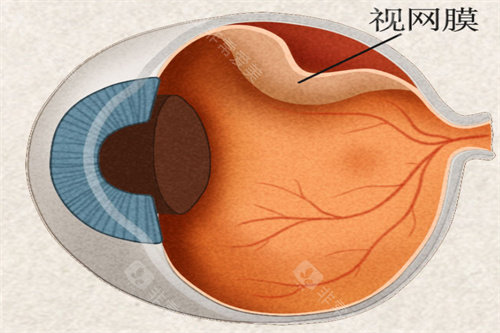

作为首都医学大学附属北京同仁医院眼底病科的“定海神针”,他擅长复杂眼底病诊疗,尤其对视网膜脱离、糖尿病视网膜病变等疾病的手术处理堪称业内标杆。